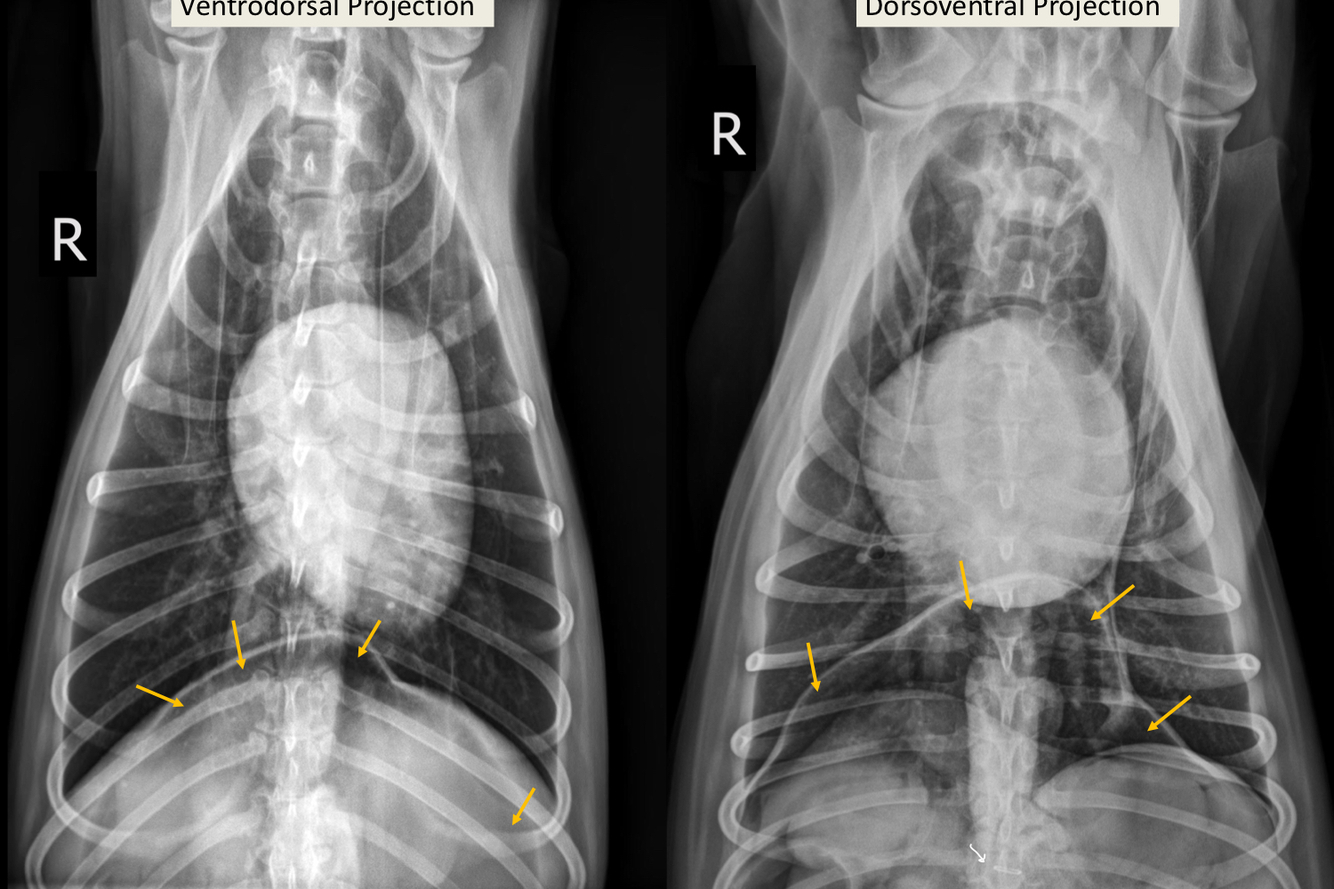

What is seen in these thoracic radiographs?

A

• sternal lysis and collapse with soft tissue swelling

• multiple, small pulmonary nodules

• osteolytic diaphysis and osteophyte formation